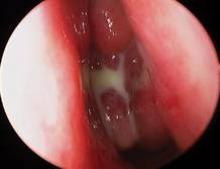

Photo courtesy Intersect ENT.

The steroid-releasing sinus stent is shown in the ethmoid cavity.